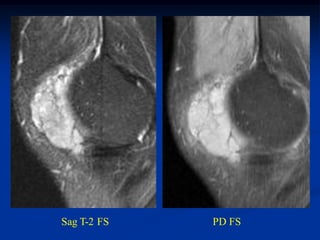

Case #362.3          Axial T-2              Synovial sarcoma

40 year male with knee pain for 6 months

Cor T-1      T-2

PD FS

Sag T-2 FS   PD FS